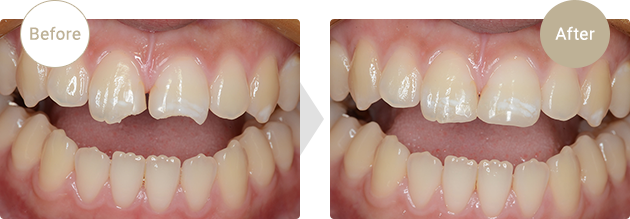

症例.03

歯冠破折

転倒により歯冠破折。合成樹脂(レジン)にて即日修復しました。